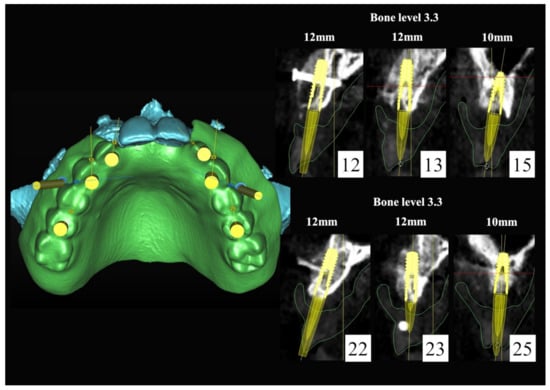

The number, the length, the diameter and the placement of computational virtual implants were determined with respect to the design of the final prosthesis the available residual bone volume and the anatomical limitations according to the previously described technical procedure (Figure 16, Figure 17, Figure 18, Figure 19, Figure 20 and Figure 21).

Figure 16.

Three-dimensional (3D) CBCT scan images with the patient wearing the planned prosthesis.

Figure 17.

Three-dimensional (3D) CBCT scan images of the prosthesis equipped with integrated radiopaque reference spheres scanned separately.

Figure 18.

Three-dimensional (3D) planning of the number, the diameter and the axis of dental implants with respect to the design of the final virtual maxillary prosthesis.

Figure 19.

Figure 20.

Maxillary and mandibular virtual surgical drilling guides designed according to the implant position.

Figure 21.

Final maxillary and mandibular stereolithographic surgical drilling guides.

6.2.4. Intra-Operative Documentation:

In March 2013, twelve guided dental implants were placed at sites # 12, # 13, # 15, # 22, # 23, # 25, # 33, # 34, # 36, # 43, # 44, and # 46 (Figure 22, Figure 23, Figure 24, Figure 25 and Figure 26)